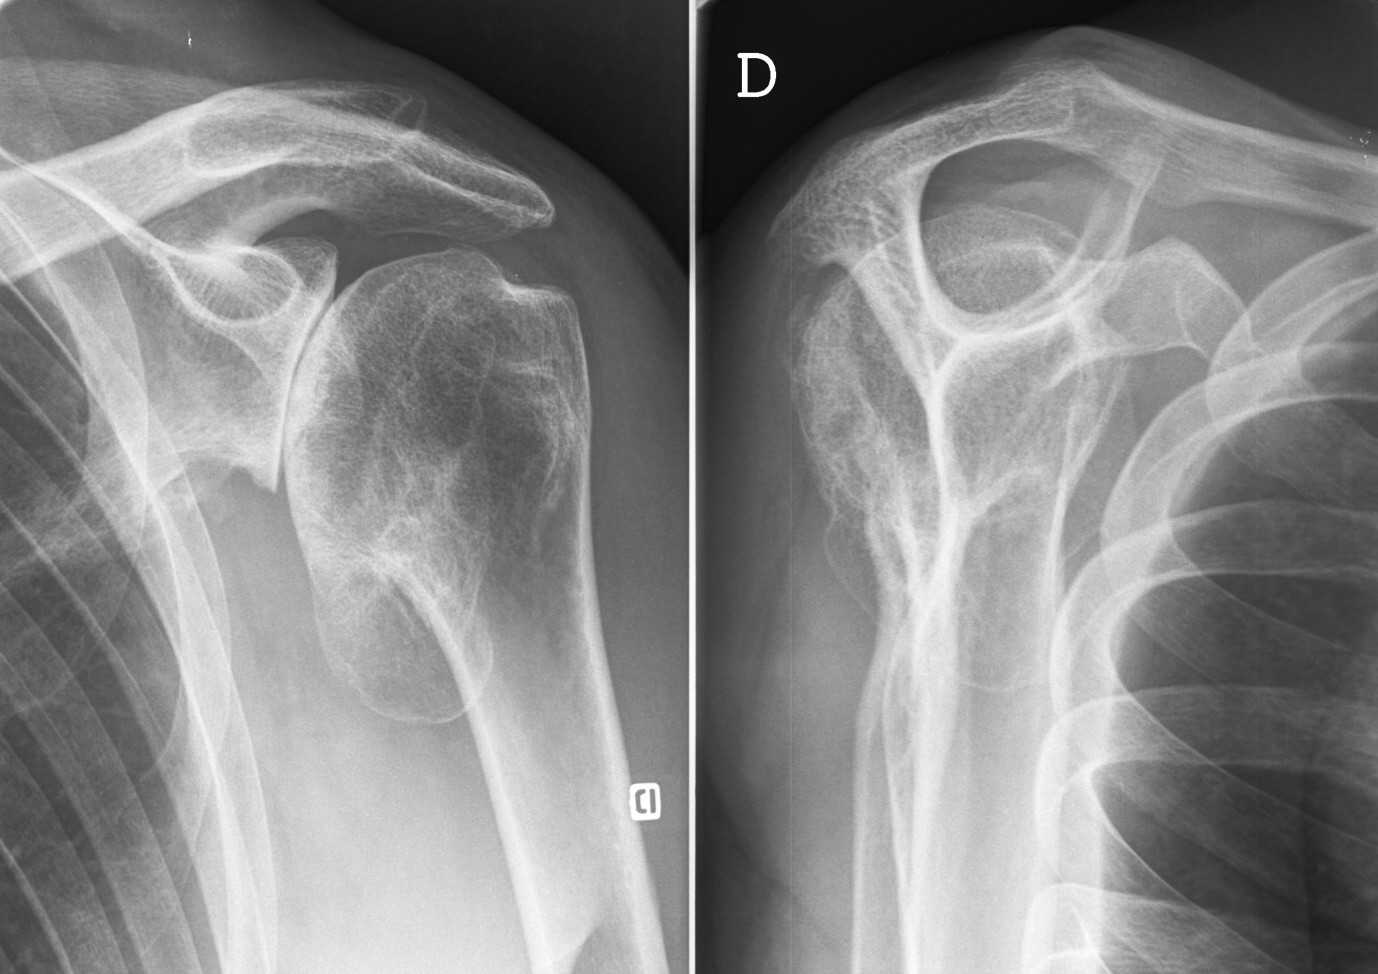

L'omarthrose est une dégradation du cartilage de votre épaule qui peut évoluer de différentes façons. Immobilisation coude au corps pendant 15 jours. L'arthrose de l'épaule ou « omarthrose » est une dégradation du cartilage de l'épaule qui peut évoluer de différentes façons. Les prothèses totales d'épaule anatomiques et les prothèses totales d'épaule inversées. L'épaule est immobilisée avec une écharpe simple pour une durée d'1 mois, la rééducation est néanmoins débutée immédiatement. Récupérer l'extension rapidement, la flexion viendra toute seule. Cabinet du docteur pierre moulinoux. Une rééducation à la fois précoce et adaptée qui à. Toutefois, ceci ne signifie pas qu'il faille poursuivre une rééducation quotidienne à long terme, mais cette rééducation, si elle doit être fractionnée et. 6 mois avec un kinésithérapeute puis 6 mois seul(e) en auto rééducation. Retrouvez toutes les vidéos de chirurgie orthopédique sur la chaine youtube du dr. La rééducation peut être réalisée dans un centre ou auprès un kinésithérapeute spécialisé. La rééducation sera débutée le plus rapidement possible en fonction du type de prothèse implantée. Methode une etude multicentrique prospective a ete menee pour analyser les resultats de 671 patients (âge moyen : La partie sphérique est fixée une rééducation avec un kinésithérapeute sera nécessaire pour restaurer la mobilité puis la force. Une prothèse sert à remplacer la tête de l'humérus puisque le cartilage est usé. Mais si seul un de ces deux. Elle donne d'excellents résultats sur la douleur (plus de 85 % des patients indolores ou. La rééducation dure environ six mois. L'hospitalisation est de 4 à 5 jours avec dans les suites le port d'un coude au corps pendant trois semaines. Prothèse de l'épaule en cas d'arthrose avancée ou de lésions étendues. Buts de la rééducation : Rédigé par des auteurs spécialisés ooreka. La rééducation dépendra du type d'intervention et devra s'adapter. Le protocole de rééducation dépend de la technique chirurgicale, des tendons qui ont été éventuellement détachés et de la tenue de la prothèse. Une prothèse est un ensemble d'éléments une prothèse totale inversée permettant de pallier à l'insuffisance des muscles rotateurs de l'épaule. Il existe 2 types de prothèse : Le lendemain de l'intervention, le. Il existe plusieurs sortes de prothèses. Rééducation suite à une prothèse. Cette prise en charge associe le patient, le chirurgien et le kinésithérapeute.